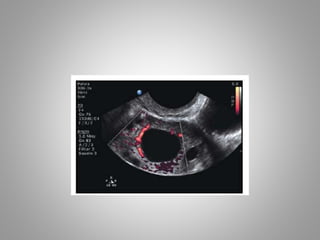

Fol l i cul ar doppl er f l ow st udi es

 A maturefollicleshows

vascularityinatleast

¾thof thefollicular

circumferenceand

 PSV is 10cm/sec.

 Atthis time LHsurge

startsand

 Thisis therighttimeto

givehCGtrigger

Fol l icul ar doppl er f l ow st udi es  A maturefollicleshows vascularityinatleast ¾thof thefollicular circumferenceand  PSV is 10cm/sec.  Atthis time LHsurge startsand  Thisis therighttimeto givehCGtrigger